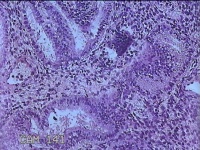

子宫腔赘生物

性别

女

年龄

33岁

临床诊断

子宫内膜息肉?子宫异常出血

一般病史

阴道流血12天。

标本名称

大体所见

灰白粉红色不规则肿物1.5x1.3x0.2cm一堆,表面糜烂。

图1